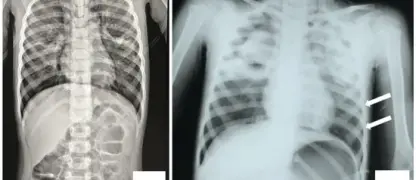

• Respiratory symptoms such as coughing, shortness of breath, and fluid accumulation in the lungs develop as HPS progresses.

• Severe cases may lead to sudden respiratory failure, low blood pressure, and organ dysfunction, requiring urgent medical attention.

Image description of Hantavirus Pulmonary Syndrome (HPS)

Hantavirus Pulmonary Syndrome is a severe respiratory disease caused by hantaviruses, typically spread by rodent contact. It affects the lungs, leading to breathing difficulties and potentially life-threatening complications.